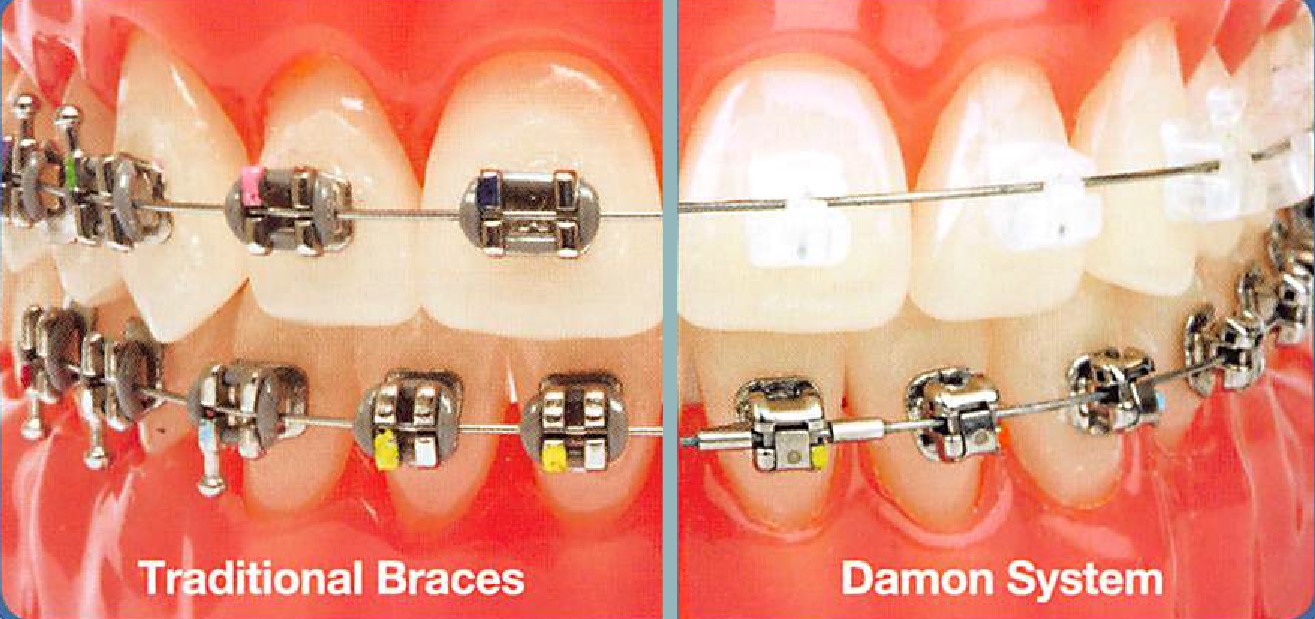

بریس های دیمون نوعی ارتودنسی ثابت هستند و در طول درمان ارتودنسی، بر روی دندان های فرد به طور ثابت قرار گرفته اند. سیستم دیمون که از جدیدترین روش های ارتودنسی دندان است، از یک روش خودتنظیم شونده استفاده می کند.

آن ها از کش ارتودنسی در اطراف براکت و به منظور اتصال سیم ارتودنسی به براکت ها استفاده نمی کنند. در عوض از مکانیزم کشویی استفاده می کنند که دندان های شما را در امتداد سیم های رابط هدایت می کند. دندان های شما در این روش، حرکت آزاد دارند تا به تدریج در امتداد سیم به جای صاف تر کشیده شوند. این باعث کاهش کشش و اصطکاک ناخواسته و بی امان ناشی از الاستیک ها می شود و باعث درمان نسبتاً کارآمدتر و راحت تر می شود.

ارتودنسی دیمون همانند بریس های سنتی ثابت، انواع مختلفی دارند که متخصص ارتودنسی با توجه به ناهنجاری و همچنین با در نظر گرفتن سلیقه شما، یکی از این بریس ها را برای شما انتخاب می کند.